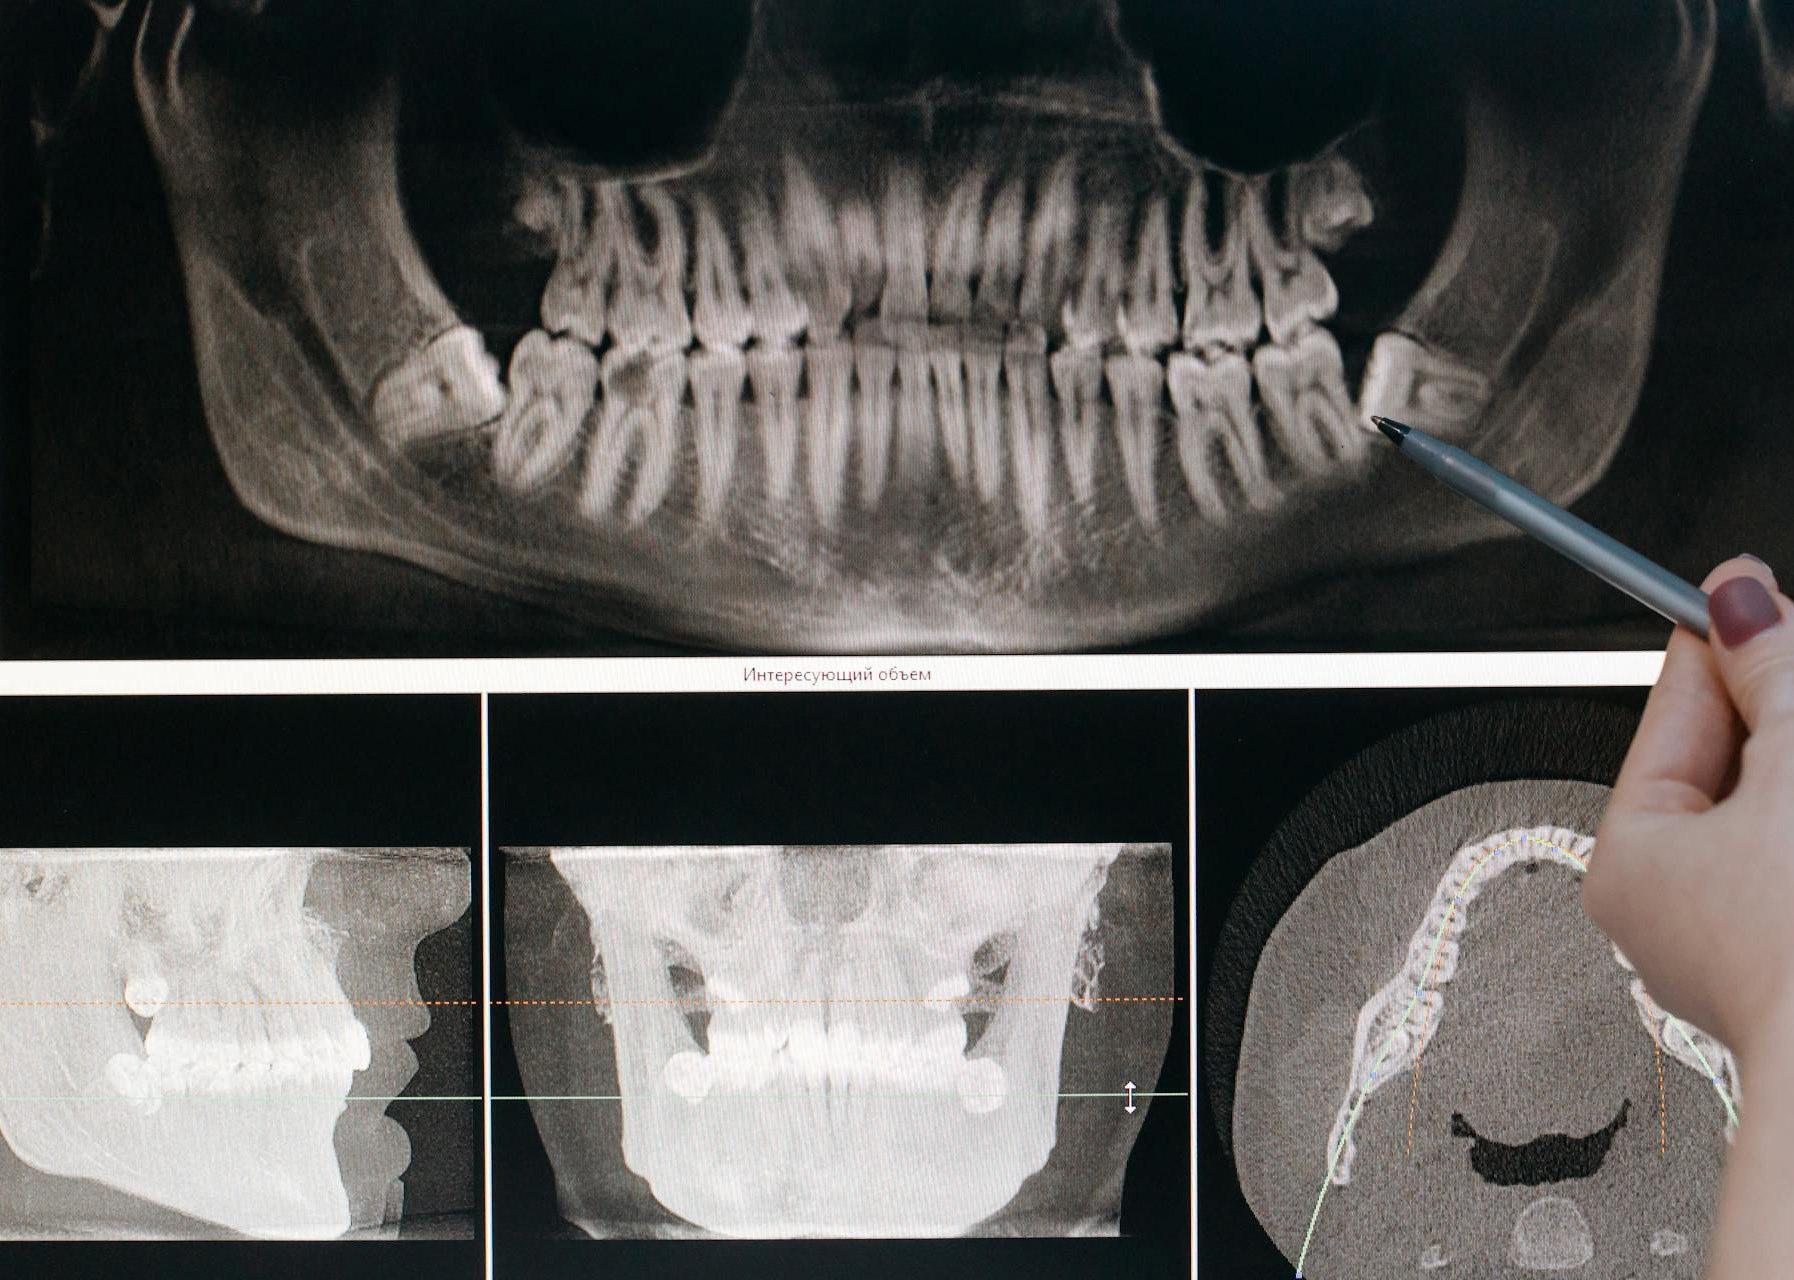

SMILE SOCIETY – A NEW ERA OF DENTISTRY

Opening May 2026

In a world where healthcare can often feel rushed and impersonal, Smile Society is setting a new standard for dentistry—one that is calm, considered, and completely centred around you.

Opening this May, Smile Society introduces a fresh approach to private dental care: unhurried appointments, tailored treatments, and a genuinely reassuring experience from the moment you walk through the door. Here, the philosophy is simple— the most important person in the room is the one in the chair.

Smile Society offers a full spectrum of care for individuals and families alike. From routine checkups and hygiene appointments to advanced cosmetic and restorative treatments, every service is delivered with precision, transparency, and affordability in mind.

The Hidden Cause of Tooth Decay: It’s Not Just Sugar… It’s Frequency

While Smile Society is focused on delivering exceptional care, prevention remains at the heart of its philosophy. And when it comes to tooth decay, there’s one key message many patients still misunderstand.

Most people believe sugar is the main culprit. But the reality is more nuanced—and far more important.

What Really Causes Tooth Decay?

Tooth decay is not simply about how much sugar you consume, but how often your teeth are exposed to acid attacks.

Each time you eat or drink something containing sugar or carbohydrates, bacteria in your mouth produces acid. This acid weakens the enamel, and your teeth need time to recover between these attacks.

Why Frequency Matters More Than Quantity

Frequent snacking or sipping—especially throughout the day—means your teeth are under constant assault, with little opportunity to repair themselves.

Even small amounts of sugar, consumed regularly, can be more damaging than a larger amount eaten in one sitting.

A Modern Lifestyle Risk

One growing trend dentists are increasingly concerned about is the rise in protein shake

consumption among gym-goers. Many of these drinks, often consumed between meals, contain hidden sugars and are surprisingly acidic.

The result? A noticeable increase in patients presenting with multiple new cavities within just a few months, alongside sensitivity and visible enamel damage.

A Preventable Problem

Left unchecked, this pattern can lead to fillings, root canal treatments, or even tooth loss. The good news, however, is that it is entirely preventable.

How to Protect Your Smile

Simple changes can make a significant difference:

• Opt for sugar-free or low-acid drinks

• Avoid sipping beverages over long periods

• Keep sugary or acidic drinks to mealtimes only

• Rinse your mouth with water after consuming them

• Maintain regular dental check-ups

A Smarter Approach to Oral Health

At Smile Society, education is just as important as treatment. By helping patients understand the real causes of dental issues, the clinic empowers them to make better choices—and avoid unnecessary procedures altogether.

Because a healthy smile isn’t just about how it looks—it’s about how it lasts.